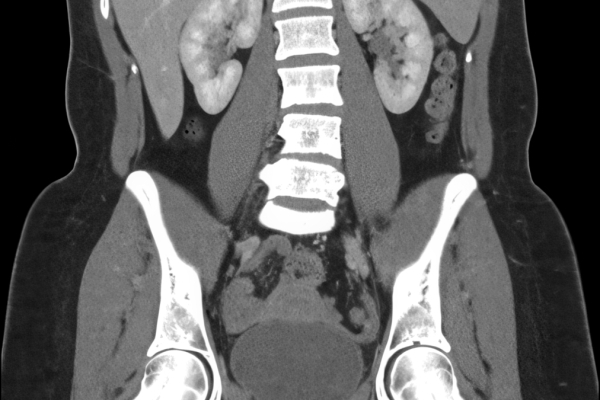

Wir verbinden modernste Medizin mit einer Atmosphäre, in der Sie sich sicher und gut aufgehoben fühlen. Klare Abläufe, Ruhe und Zeit für Sie stehen im Mittelpunkt jeder Untersuchung. CT- und MRT-Bilder ohne Wartezeit. Mit Photon-Counting-CT und 3-Tesla-MRT setzen wir auf in Kärnten einzigartige Technologien für außergewöhnlich detailreiche Bilder und besonders präzise Diagnosen. Die schonenden Verfahren eignen sich auch für Kinder und Jugendliche. Kurze Messzeiten, große offene Geräte und ein ruhiges Umfeld sorgen für eine angenehme Untersuchung und ein gutes Gefühl von Anfang bis Ende.

Wir bieten ein breites Spektrum an Untersuchungen an, von Standarduntersuchungen der Gelenke, Organe oder großflächigen Körperregionen bis zu Spezialuntersuchungen zum Beispiel des Herzen oder der Gefäße. Zusätzlich werden Angiographien (Darstellung von Blutgefäßen), Endometriose-Abklärungen und Mamma-Untersuchungen durchgeführt. Genauere Details können Sie der MRT/CT-Übersicht und der Preisliste entnehmen, oder Sie wenden sich direkt an unser Team, das Sie gerne zur passenden Untersuchung berät.

Die MRT (Magnetresonanztomographie) arbeitet mit Magnetfeldern und Radiowellen und eignet sich besonders für Untersuchungen der Weichteile wie Gehirn, Muskeln oder Gelenke. Die CT (Computertomographie) nutzt Röntgenstrahlen und liefert schnelle, hochauflösende Bilder, insbesondere für Knochen, Lunge oder innere Organe. Die Wahl der jeweiligen Untersuchung richtet sich an das individuelle Krankheitsbild und wird bei der Überweisung festgelegt.